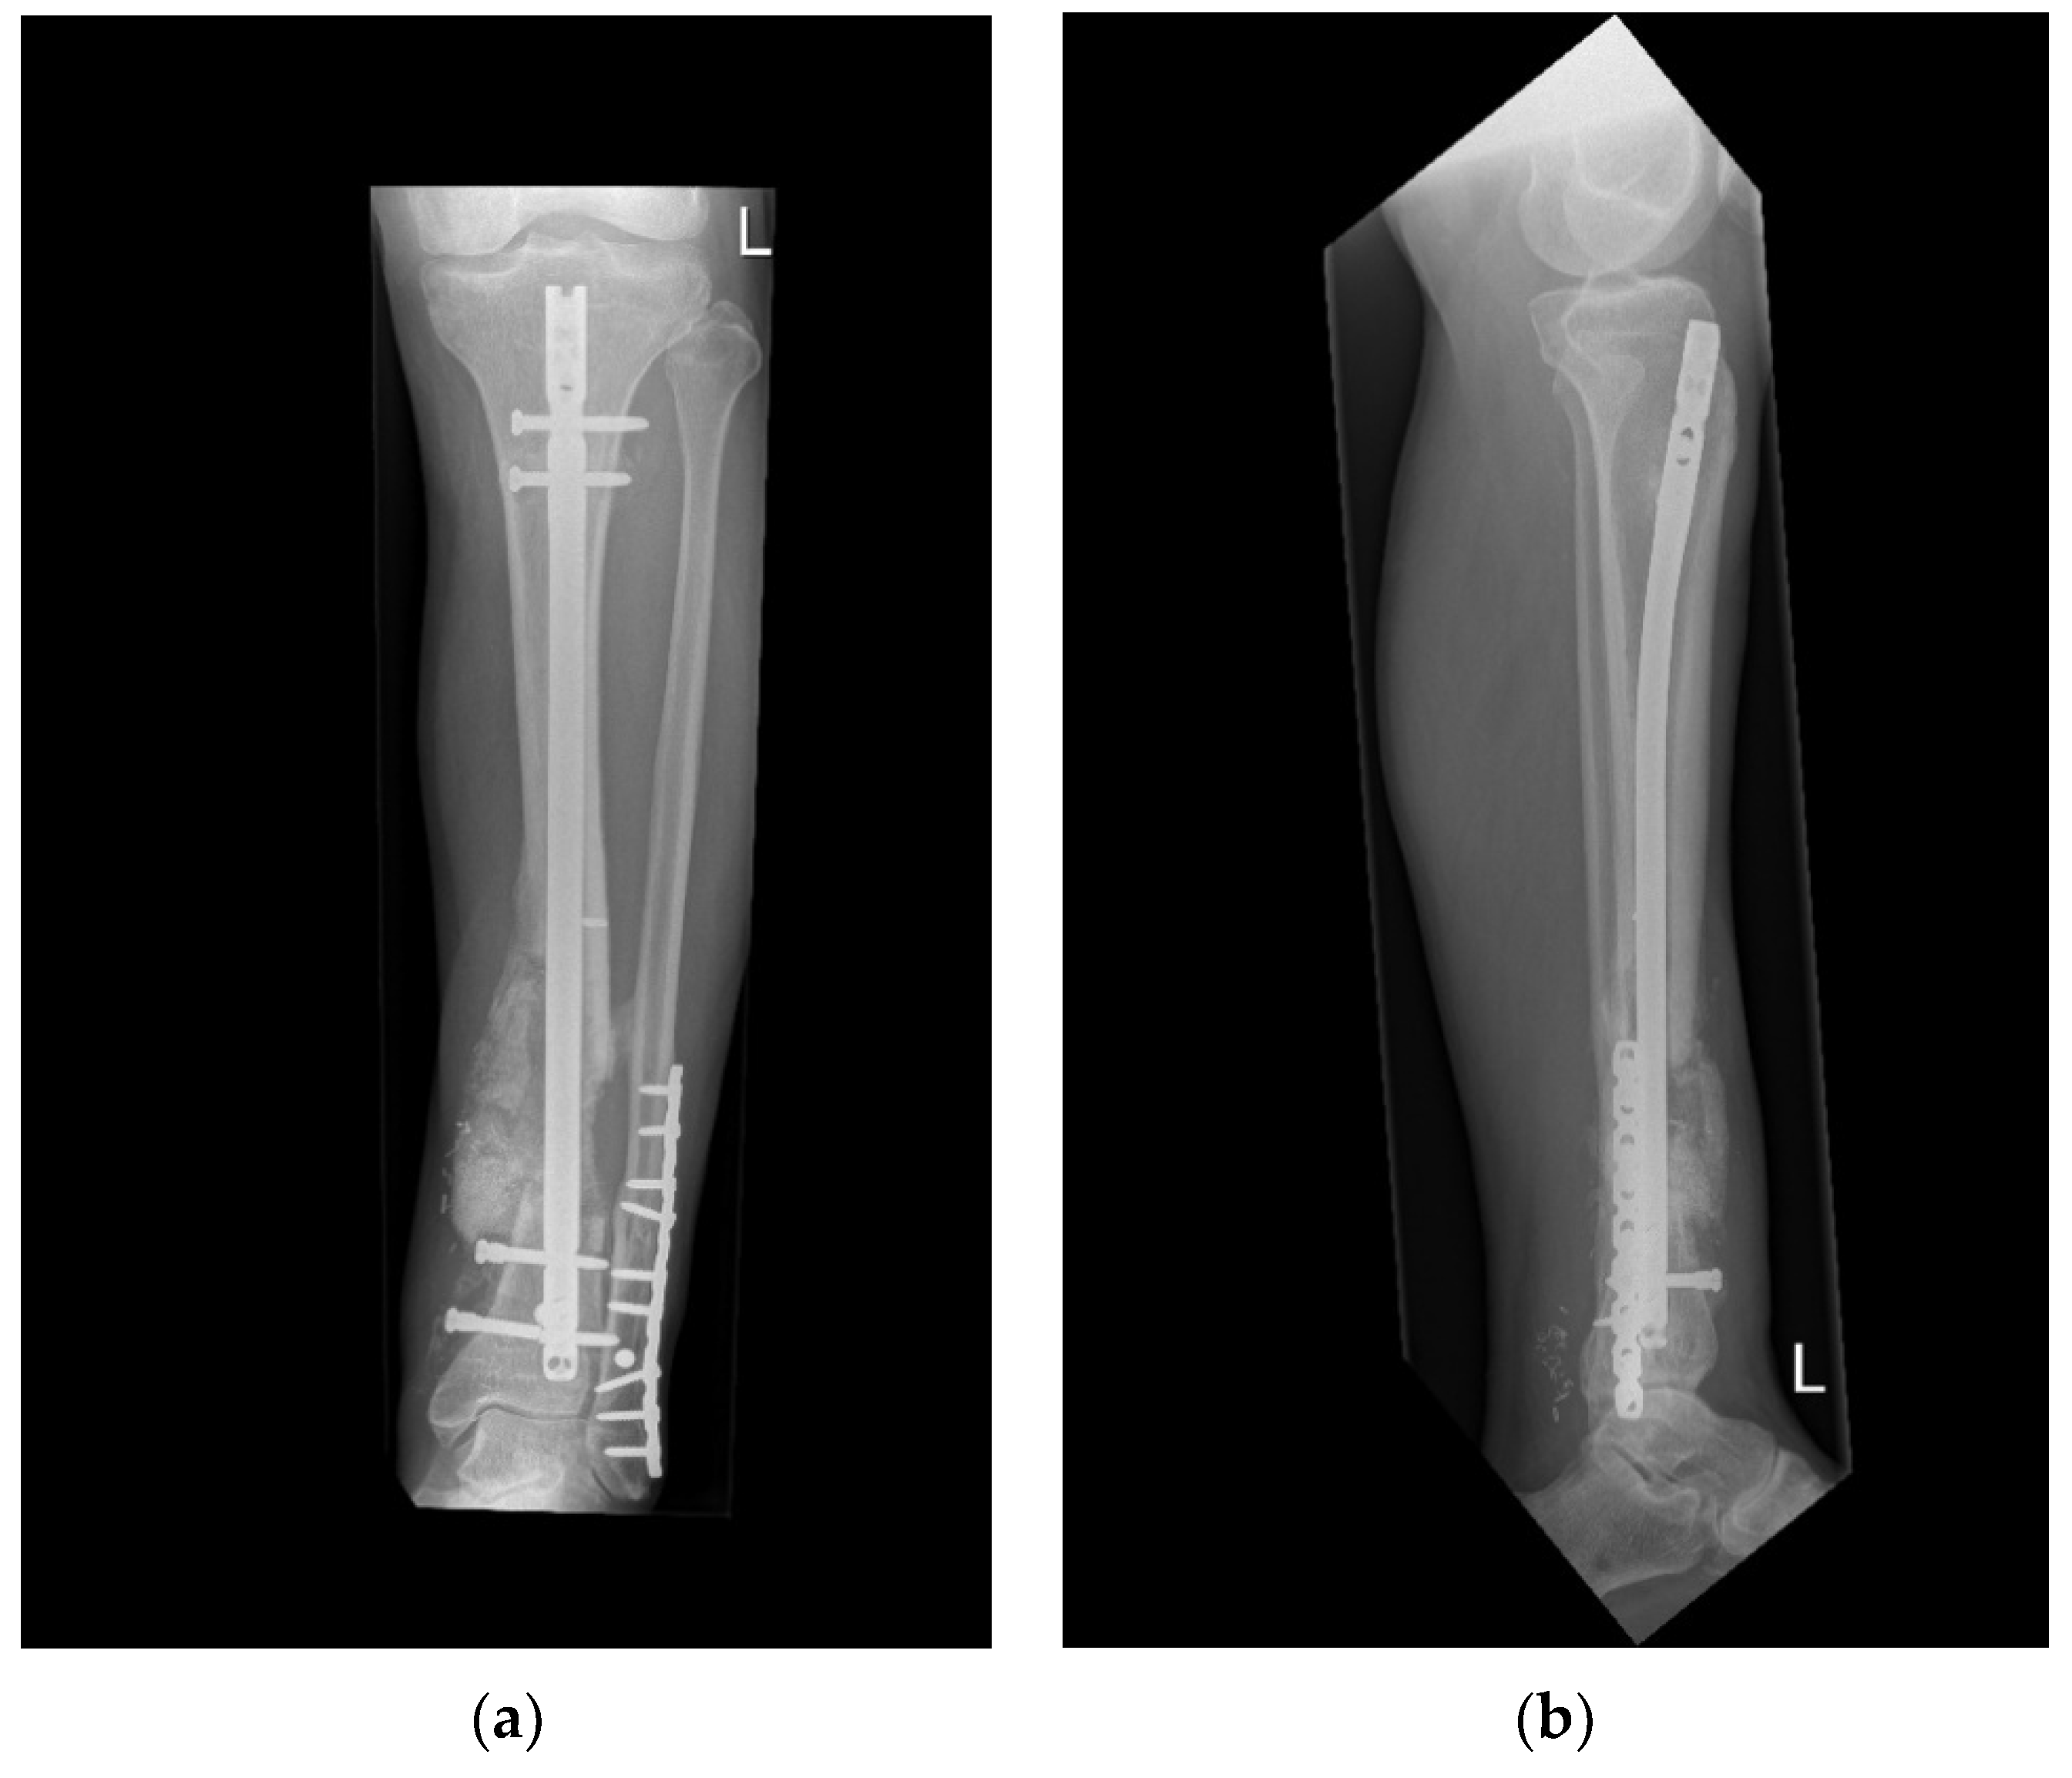

Surgical Procedures